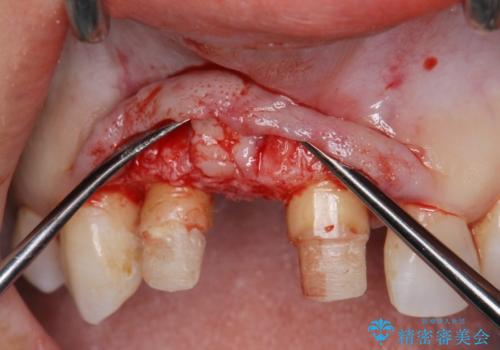

現在装着されているブリッジを除去したところ、歯ぐきよりも上に存在する歯質(縁上歯質)が少なく、土台の形態の悪さや不適合などさまざまな問題があります。

根管治療を行ったのち、歯周外科を行うことで、欠損部の歯ぐきの厚みを出し、縁上歯質を獲得することで、長期的な予後の見込めるブリッジを製作できる環境を整備していきます。